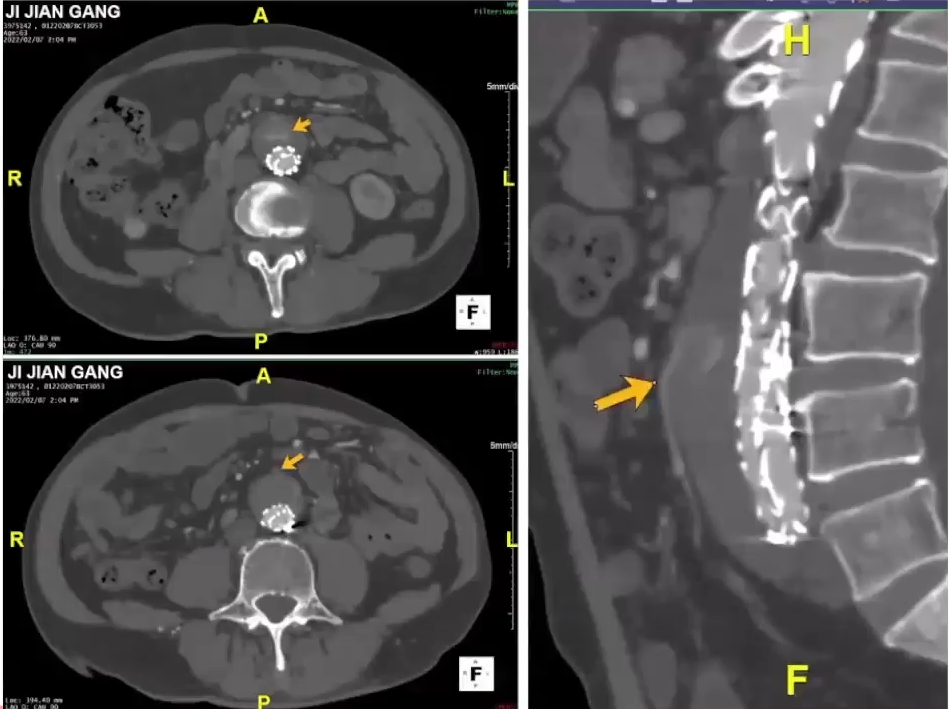

病例分享2

该患者为三期手术,除了第一次在外院手术外,之后在本院行两次手术。在第二期手术时,进行主髂和内脏区四分支重建术。1月后行第三期主髂段手术,此时可以清楚观察到潜在的内漏,并在第三期手术行内漏补救措施。该内漏是由内脏区右肾动脉真假腔供血引起,用Viabahn延长右肾动脉来做覆盖。在近期随访中,内脏区的内漏完全消失了,正好体现第三阶段主髂段进行修补的理念。

6月后,lc型内漏的补救处理